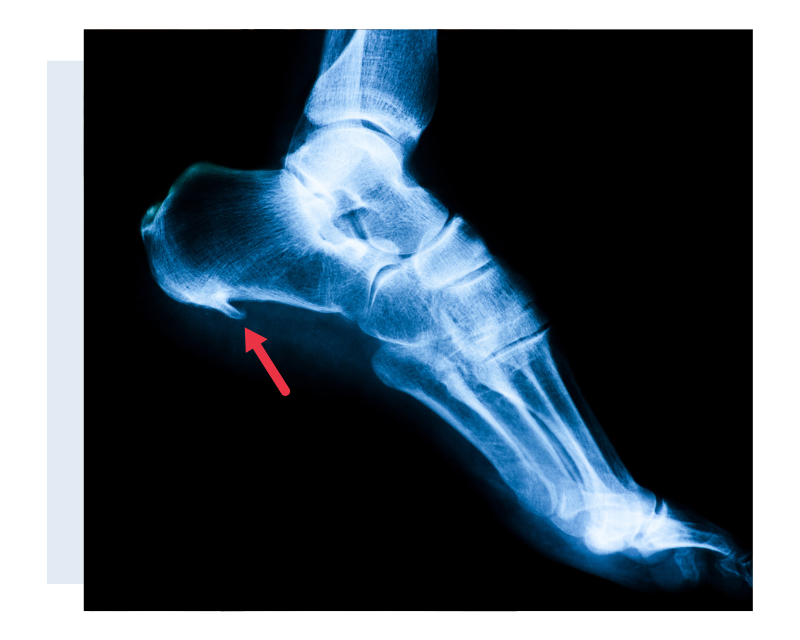

Sabe aquele esporão que insiste em aparecer no seu calcanhar? Pois é, ele é uma calcificação que surge no osso, bem na parte de baixo do calcâneo (o osso do seu calcanhar). Pensa nele como um pequeno “bico” de osso que se forma. Ele aparece justamente ali porque é um ponto de muita pressão e tensão na nossa pisada. A faixa de tecido que liga o calcanhar aos dedos, a fáscia plantar, sofre um estresse constante, e o corpo, na tentativa de proteger, cria essa estrutura óssea.

Muitas vezes, o que a gente precisa é de uma orientação profissional para entender o que está acontecendo e qual o melhor caminho para tratar a dor no calcanhar por esporão. Um médico, como um ortopedista, pode fazer o diagnóstico correto e indicar o tratamento mais adequado para você. E não se preocupe, geralmente não é nada complicado.

Dica Prática: Se a dor for muito intensa e persistente, procure um médico ortopedista. Ele poderá solicitar exames, como um raio-X, para confirmar o esporão e indicar o tratamento ideal, que pode incluir fisioterapia e o uso de palmilhas específicas.